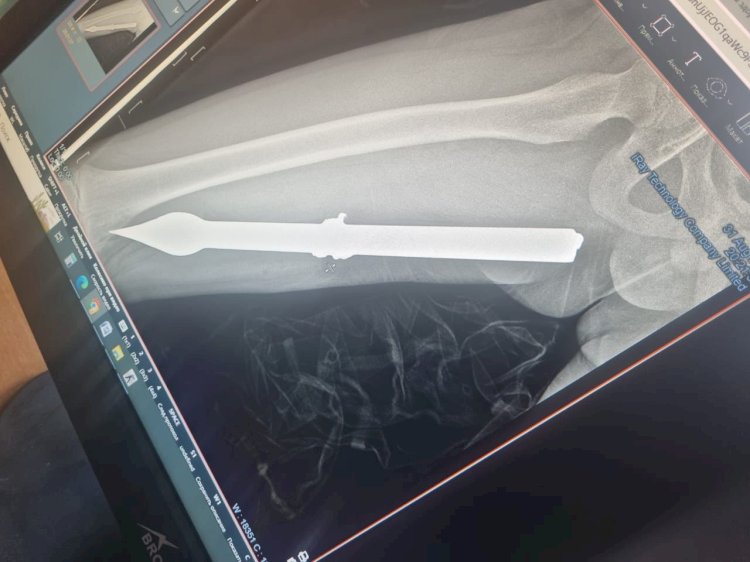

10 жасар баланың аяғына темір істік кіріп кетті

Жасөспірім қоршаудан асып өтпек болғанда оның аяғын темір тесіп кетіп, 20 сантиметрлік істікке ілініп қалған. Алматы қалалық балаларға арналған жедел медициналық көмек орталығының хирургтері...

04.09.2023 03:17 • 1,340 көру